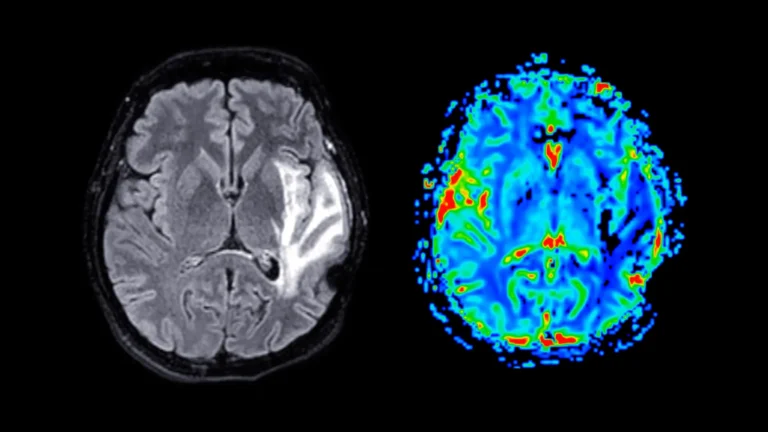

The precise mode of action for Mic-628 involves its direct interaction with CRY1, a protein that ordinarily exerts an inhibitory influence on the activity of clock genes. This molecular engagement facilitates the assembly of a more substantial protein complex, identified as CLOCK-BMAL1-CRY1-Mic-628. Upon its formation, this augmented complex initiates the transcription of Per1 by binding to a particular segment of DNA known as a "dual E-box." This sophisticated biochemical pathway enables Mic-628 to orchestrate a temporal recalibration of both the central pacemaker situated in the brain’s suprachiasmatic nucleus (SCN) and the peripheral biological clocks present in various organs, including the pulmonary system. A critical observation from these studies was the synchronized nature of these clock shifts, occurring uniformly across different tissues and irrespective of the temporal administration of the compound.